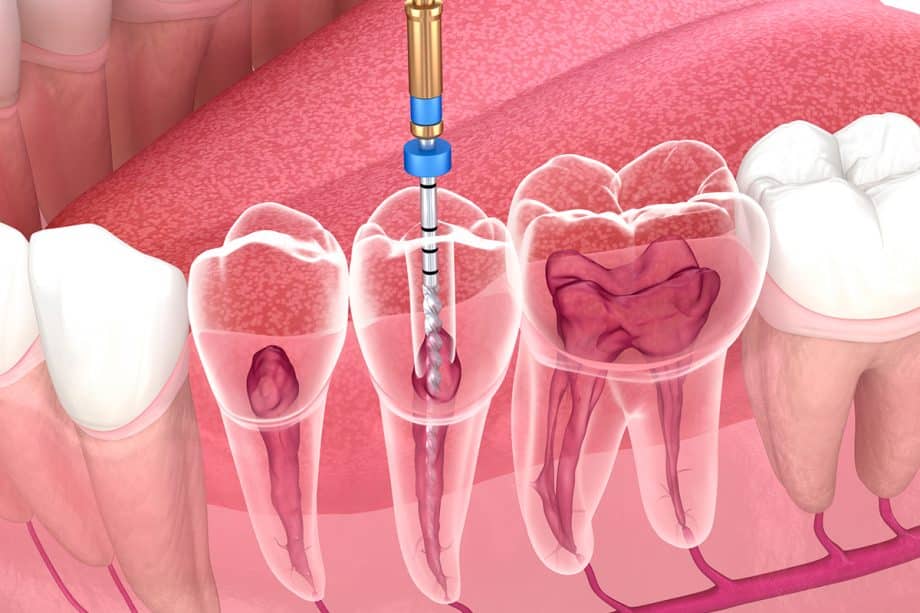

تتم خطوات علاج عصب الأسنان في جدة بطريقة دقيقة ومنظمة للحفاظ على السن وتخفيف الألم بشكل آمن وفعال. يبدأ طبيب الأسنان بفحص سريري دقيق وتصوير بالأشعة لتشخيص حالة عصب السن وتحديد مدى الالتهاب أو التلف. بعد ذلك يقوم بتخدير موضعي للسن لضمان راحة المريض، ثم يفتح تاج السن للوصول إلى قنوات العصب الملتهبة. يتم تنظيف قنوات الجذور بعناية باستخدام أدوات خاصة لإزالة العصب المصاب وبقايا البكتيريا، مع غسل القنوات بسوائل مطهرة لمنع العدوى. بعد الانتهاء من التنظيف والتطهير، تُجفف القنوات جيدًا ثم تُحشى بمادة خاصة لإغلاقها بإحكام ومنع عودة البكتيريا. في الخطوة الأخيرة، يُعاد بناء السن وترميمه إما بحشوة دائمة أو تركيب تاج (كراون) حسب حالة السن لضمان متانته ووظيفته على المدى الطويل. الالتزام بهذه الخطوات المتكاملة في علاج عصب الأسنان في جدة يساعد على إنقاذ السن الطبيعي وتخفيف الألم والحفاظ على صحة الفم والأسنان.

يضم مركز وعيادات بطل للأسنان نخبة من أفضل أطباء علاج العصب في جدة، ممن يمتلكون خبرة واسعة في تشخيص وعلاج التهاب عصب الأسنان وإنقاذ الضروس قبل الحاجة للخلع.يعتمد الأطباء على أحدث تقنيات علاج عصب الأسنان (حشو العصب المجهري، أجهزة الروتاري، والتصوير الرقمي ثلاثي الأبعاد) لضمان تنظيف القنوات الجذرية بدقة عالية وتقليل الألم إلى أدنى درجة ممكنة.تتميز عيادات بطل للأسنان في جدة بتطبيق بروتوكولات تعقيم صارمة واستخدام مواد حشو عصب عالية الجودة تدوم لسنوات، ما يرفع من نسب نجاح علاج العصب ويحافظ على السن الطبيعي لأطول فترة.إذا كنت تبحث عن أفضل دكتور عصب أسنان في جدة أو أفضل عيادة علاج عصب مع ضمان ونتائج موثوقة، فإن عيادات بطل للأسنان تقدم رعاية متكاملة تبدأ من التشخيص الدقيق مرورًا بعلاج العصب وانتهاءً بترميم السن بتلبيسات تجميلية قوية تحافظ على الشكل والوظيفة.هذه المنظومة المتكاملة تجعل عيادات بطل للأسنان خيارًا مفضلًا لمن يبحث عن علاج عصب الأسنان في جدة باحترافية عالية وتجربة علاج مريحة وآمنة.